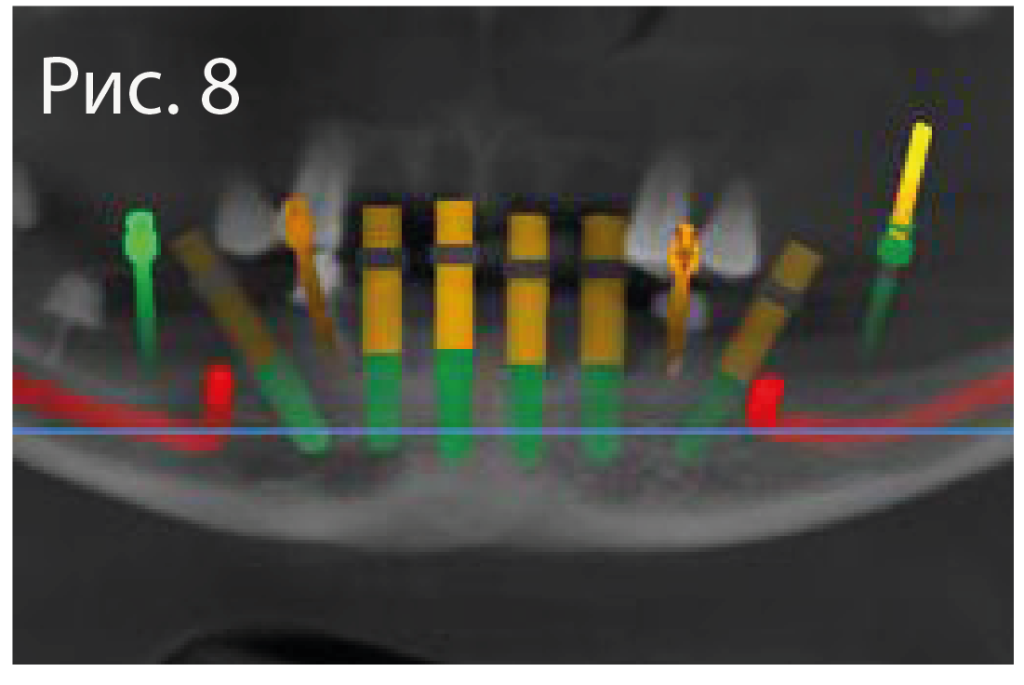

8.png

Виртуальное планирование имплантации на нижней челюсти